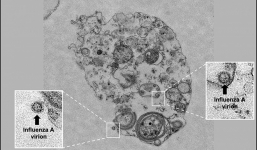

Phát hiện cách lây nhiễm mới của virus cúm